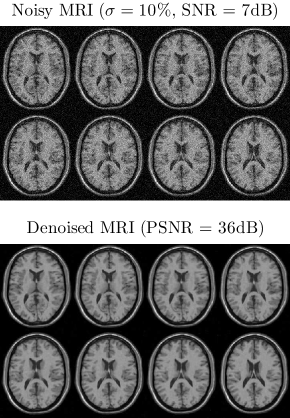

The key difference between (30) and (26) lies in the multilinear structures of 𝐀¯k(1)subscriptsuperscript¯𝐀1𝑘\mathbf{\bar{A}}^{(1)}_{k} and 𝐀˘k(1)subscriptsuperscript˘𝐀1𝑘\mathbf{\breve{A}}^{(1)}_{k} shown in (31).

We call (29) or (30) CIFA-Tucker as the constrained Tucker decomposition model is a key model of this linked component analysis. To solve this problem, we may apply the ALS method used in JIVE, but with additional multilinear structure constraints imposed on 𝐀¯k(1)subscriptsuperscript¯𝐀1𝑘\mathbf{\bar{A}}^{(1)}_{k} and 𝐀˘k(1)subscriptsuperscript˘𝐀1𝑘\mathbf{\breve{A}}^{(1)}_{k}. Alternatively, we can apply the two-step method proposed in [93]: in the first step dimensionality reduction can be performed to obtain (29). Then, the rotational ambiguity associated with the Tucker model allows us to simultaneously rotate the columns of 𝐁k(1)subscriptsuperscript𝐁1𝑘\mathbf{B}^{(1)}_{k} and conversely the rows of 𝐆(k,1)subscript𝐆𝑘1{\mathbf{G}}_{(k,1)} to achieve the separation of common and individual subspaces. Afterwards BSS can be applied to respective subspaces to extract unique and physically meaningful common and individual components with specific properties, such as sparsity, nonnegativity, statistical independence.

More generally, multi-block high-order tensor data may share more than one mode, each of which contains some common components. To model such a complex dataset, we can combine these modes to form a big mode that may contain some common components, by reshaping each data tensor 𝓧ksubscript𝓧𝑘\boldsymbol{\mathscr{X}}_{k} simultaneously using the technique introduced in [78]. As such, the matrix 𝐁¯(1)superscript¯𝐁1\mathbf{\bar{B}}^{(1)} in (30) is replaced by the Kronecker product of common components coming from different modes. In other words, we can impose additional structure constraints upon 𝐁¯(1)superscript¯𝐁1\mathbf{\bar{B}}^{(1)} and 𝐁˘k(1)subscriptsuperscript˘𝐁1𝑘\mathbf{\breve{B}}^{(1)}_{k}. This problem can be solved using the ALS [78]; implementation details are however omitted due to space limitation.

TABLE III: Comparison of popular dimensionality reduction models (c.f. [97]). 𝐘I×T𝐘superscript𝐼𝑇\mathbf{Y}\in\mathbb{R}^{I\times T} is the data matrix of T𝑇T samples in I𝐼I-dimensional space, 𝐗=𝐀𝐁𝐗superscript𝐀𝐁top\mathbf{X}=\mathbf{AB}^{\top} is the extracted low-rank data, the sparse matrix 𝐄𝐄\mathbf{E} denotes the outliers. Laplacian matrix 𝚽𝚽\mathbf{\Phi} characterizes a simple graph or a hypergraph between the samples of 𝐘𝐘\mathbf{Y} [97], L2,1subscript𝐿21L_{2,1} norm is defined as 𝐘2,1=t=1T𝐲t2subscriptnorm𝐘21superscriptsubscript𝑡1𝑇subscriptnormsubscript𝐲𝑡2\left\|\mathbf{Y}\right\|_{2,1}=\sum_{t=1}^{T}\left\|\mathbf{y}_{t}\right\|_{2}. Due to space limitation, most of their nonnegative variations are omitted here as they are straightforward, and their multiway extension can be found in [98, 99, 100] and references therein.